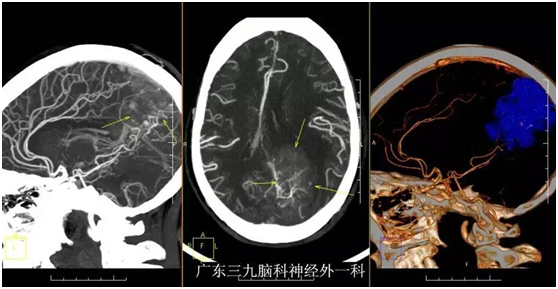

黄奶奶,72岁,因“视物模糊3个月,右侧肢体乏力半个月”入院。3个月前老奶奶无明显诱因下,出现左眼视物模糊,近半个月来出现右侧肢体乏力伴行走不稳,当地医院颅脑MR检查示:左侧枕叶镰窦旁占位性病变,门诊拟“左侧枕叶镰窦旁脑膜瘤”收入我院。入院视力1米数指。入院后完善相关检查,在全麻下行左侧枕叶镰窦旁脑膜瘤切除,手术后恢复良好,老奶奶视物较前改善,能下地行走。

广东三九脑科医院神经外一科主任张良教授分析:脑膜瘤良性,以中、老年女性多发,增长缓慢,多在较大造成症状时(如肢体麻木、瘫痪、癫痫等)才被检查发现。颅内好发部位:凸面脑膜、窦旁、鞍结节、嗅沟、桥小脑角、脑室脉络丛、蝶骨脊等。手术全切是治疗的主要措施。个别重要功能区,可采取谨慎态度处理,如立体定向放射治疗,以控制延缓瘤体增长速度。极个别脑膜瘤有恶性倾向,可表现为多发,甚至发生颅骨侵犯,预后相对较差。